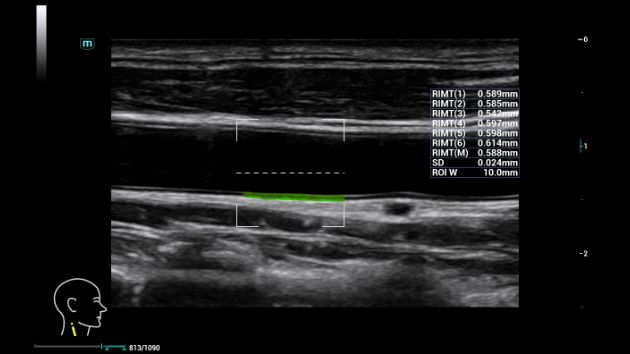

RIMT

Misurazione IMT in tempo reale basata su dati RF

Misurazione automatica ad alta precisione e in tempo reale per migliorare la diagnosi precoce delle patologie cardiovascolari e l'efficacia del successivo trattamento farmacologico.

Consona Series Cardiovascular Solution - RIMT feature clinical image